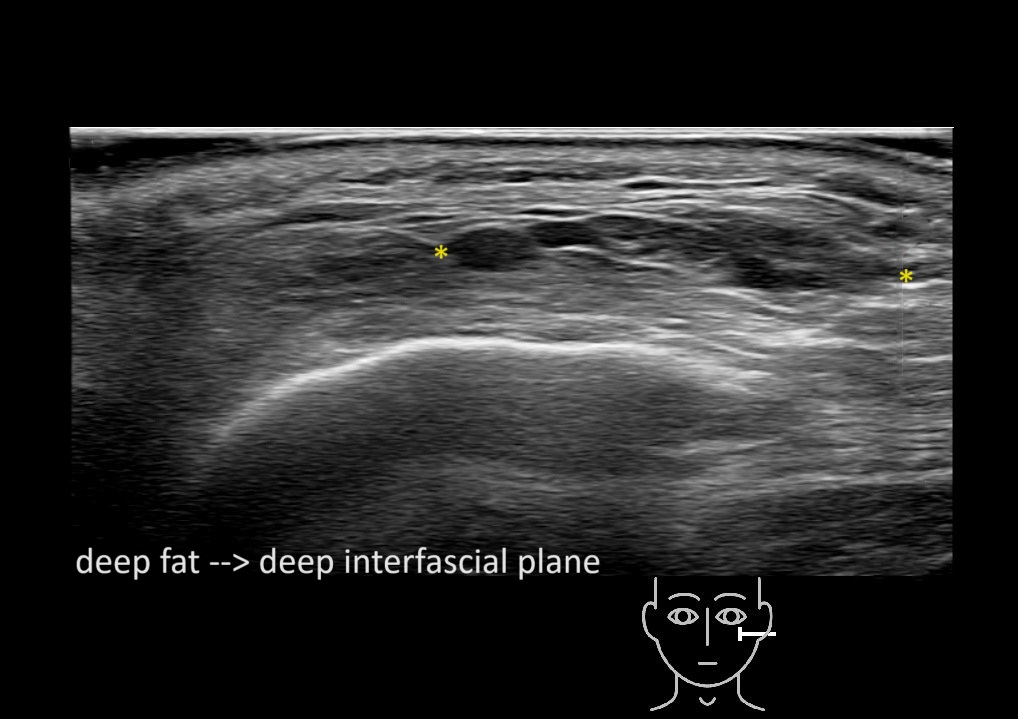

Filler behavior - Temple zygoma US

Study the first image to recognize the different layers. If you are sure about the layers, swipe to the second image to view the answer (if applicable).

Hover over an image to view the secondary image or click on the image title for more information.